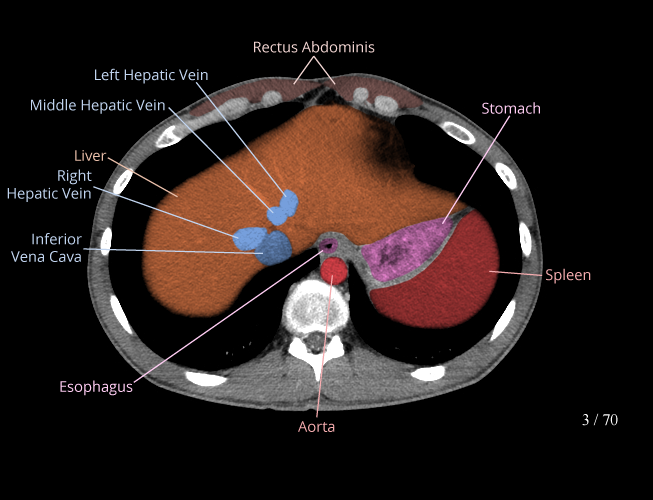

Body

Covers abdominal CT anatomy.